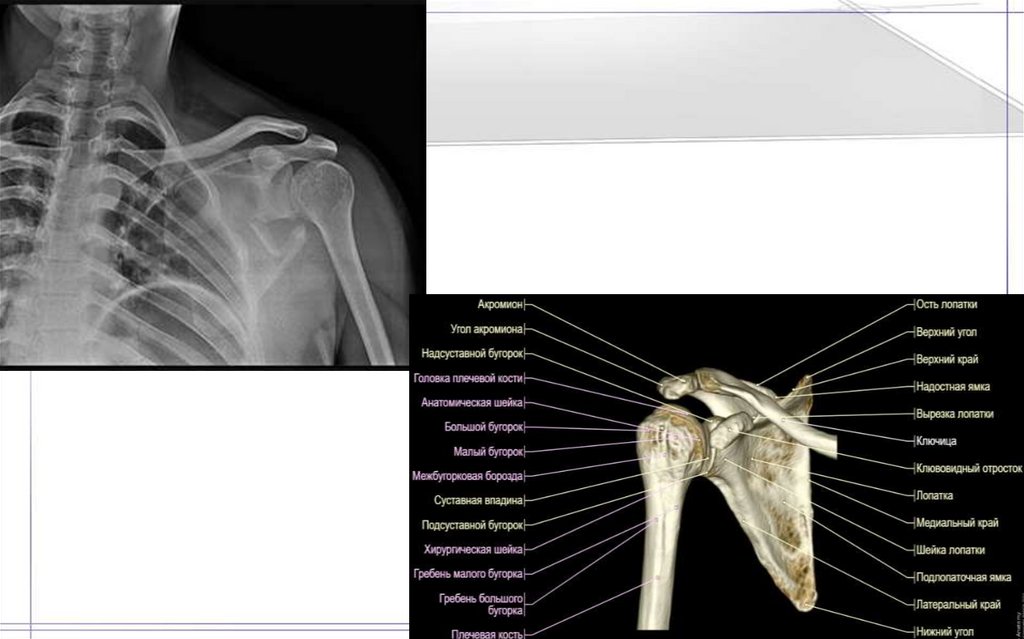

36. Плечевая кость(Humtrus)

37.

38.

39.

40.

41.

42.

43.

44.

45.

46.